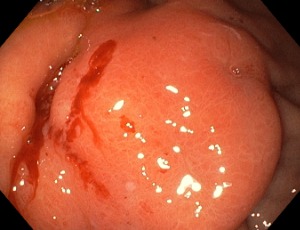

Colonic bleeding induced by a solitary juvenile polyp

A 30-year-old woman presented with 6-month history of blood-stained stools. The patient denied a family history of colon cancer. Examination was remarkable for blood-streaked stool.

J Clin Exp Gastroenterol, 2024, Volume Volume 3, Issue Issue 1, p5-6 | DOI: 10.46439/gastro.3.017